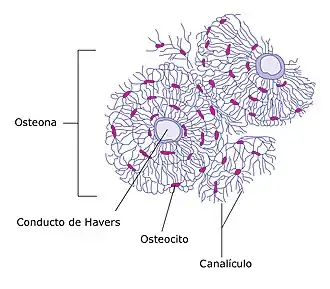

La capa exterior dura de los huesos está compuesta de hueso cortical, que también se llama hueso compacto, ya que es mucho más denso que el hueso esponjoso, su apariencia es suave, blanca y sólida, el tejido óseo compacto o hueso cortical representa el 80 % de la masa ósea del esqueleto. Se encuentra en la diáfisis o porción central de los huesos largos, en la región exterior e interior de los huesos planos y en distintas zonas del resto de los huesos. Está constituido por capas concéntricas de laminillas óseas que forman estructuras cilíndricas llamadas osteonas,.

Facilita las funciones principales de los huesos: dar apoyo a todo el cuerpo, proteger los órganos, proporcionar palancas para el movimiento y almacenar y liberar elementos químicos, principalmente calcio. Consiste en múltiples columnas microscópicas, cada una de las cuales se llama osteón o sistema de Havers.

En el centro de los osteonas se encuentran los conductos de Havers por donde transitan los vasos sanguíneos. Los conductos de Volkmann transversales sirven para conectar varios conductos de Havers entre sí. La estructura resultante podría considerarse como un conjunto de columnas unidas por lo que presenta gran resistencia a las fuerzas de compresión.[7]

En las laminillas se ubican lagunas embutidas en el matriz mineralizada que contienen osteocitos (célula principal del tejido óseo), desde cada laguna irradian pequeños canalículos ramificados que las comunican entre sí y hacen posible la nutrición de las células.[7]